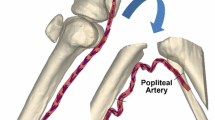

MacTaggart JN, Phillips NY, Lomneth CS et al (2014) Three-dimensional bending, torsion and axial compression of the femoropopliteal artery during limb flexion. J Biomech 47:2249–2256. https://doi.org/10.1016/j.jbiomech.2014.04.053

Poulson W, Kamenskiy A, Seas A et al (2018) Limb flexion-induced axial compression and bending in human femoropopliteal artery segments. J Vasc Surg 67:607–613. https://doi.org/10.1016/j.jvs.2017.01.071